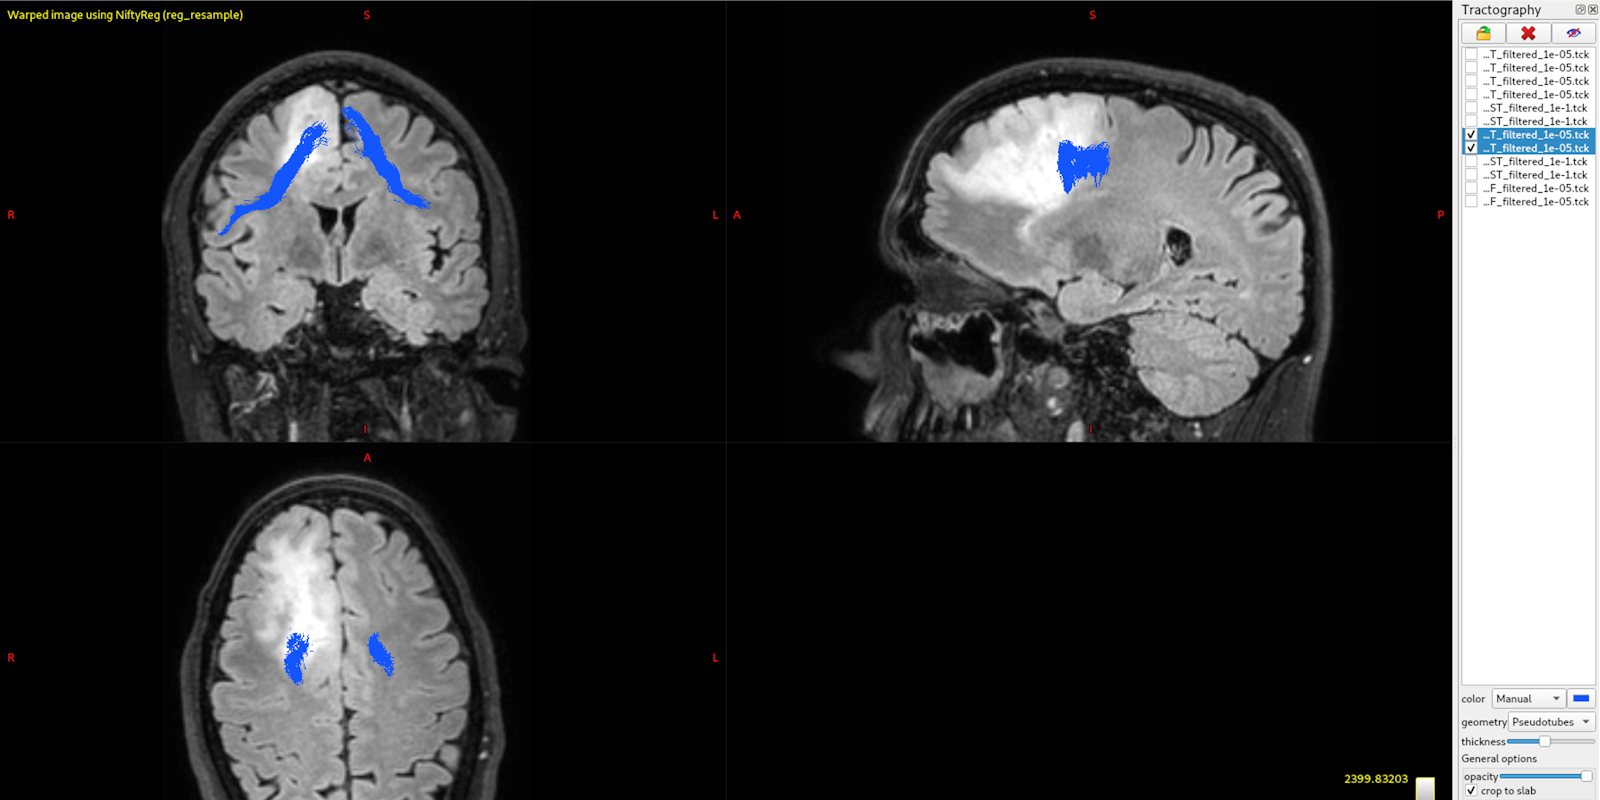

De ZonMw-subsidie (€241.004) richt zich op patiënten met een laaggradige hersentumor. Voor patiënten met een laaggradige hersentumor is het belangrijk om bij de operatie zoveel mogelijk tumor weg te halen, zonder cognitieve of lichamelijke functies te beschadigen. Ook is het belangrijk om patiënten na de operatie te vervolgen om passende zorg te bieden. De combinatie van neuropsychologische testen en MRI-tractografie helpen om deze functies te beschermen tijdens de operatie en om deze goed te kunnen vervolgen nadien. Binnen het ETZ wordt dit sinds enkele jaren bij iedere patiënt ingezet. Veel andere ziekenhuizen in Nederland gebruiken deze methoden echter nog niet standaard, terwijl dat wel in de landelijke richtlijn wordt geadviseerd. Hierdoor lopen patiënten onnodige risico’s en kans op verminderde levenskwaliteit.

In dit project willen we zorgen dat een eerder ontwikkeld ETZ protocol bestaande uit neuropsychologische screening en MRI-tractografie in alle Nederlandse ziekenhuizen wordt geïmplementeerd. We willen dit bereiken door lokale protocol aanpassingen, training van teams en evaluatie door patiënten en zorgverleners. Zo bereiken we passende zorg voor alle laaggradige hersentumor patiënten in Nederland. Vervolgens zullen de gegevens die worden verzameld met dit project worden gebruikt voor vervolgonderzoek.